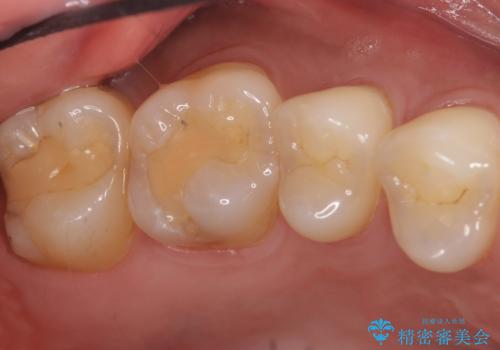

- 奥歯にフロスを通すとにおいがすることを気にされ、来院された患者様です。

精査したところ、奥歯に充填された保険内のコンポジットレジンの適合が悪いことにより、汚れがたまりやすい状態でした。

不適合なレジンを除去し、セラミックインレーによる治療を行いました。(右上76左上67右下7の計5本)